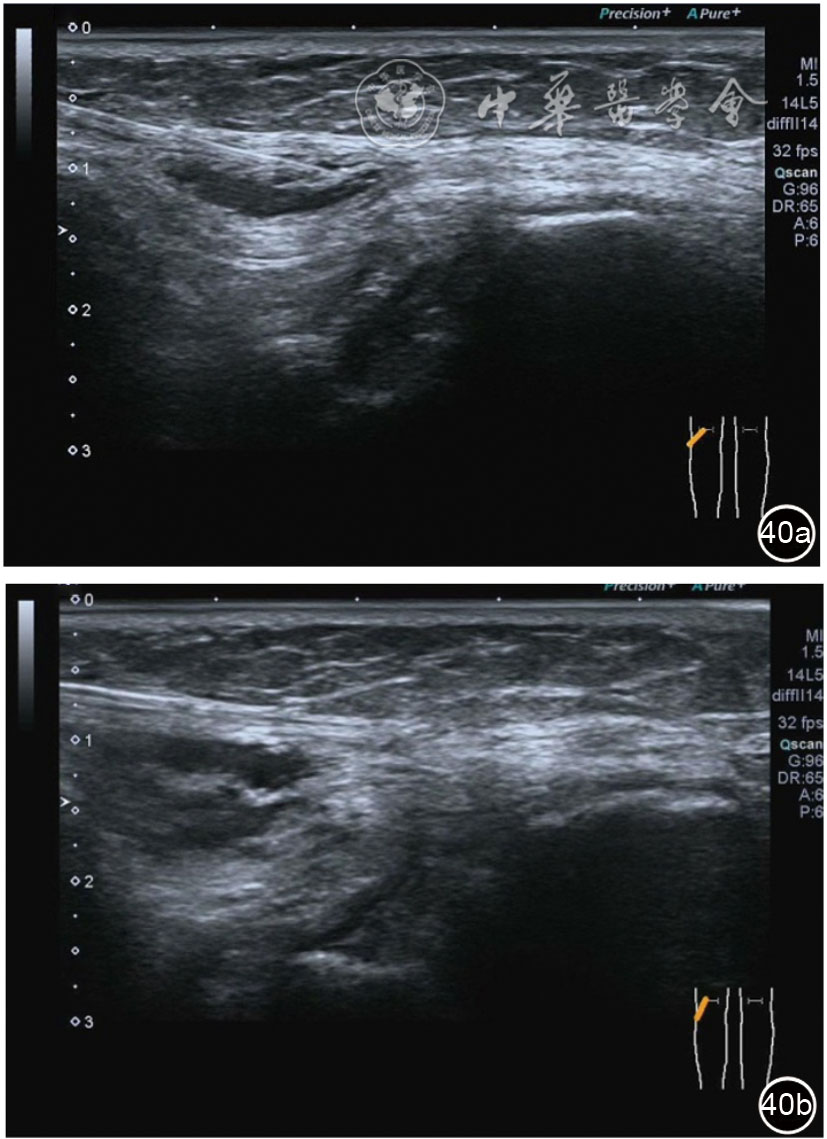

2.腓总神经卡压静态结构针刀切割松解治疗。体位与治疗前准备同局部液压松解加药物注射治疗。治疗点在卡压最明显的部位,一般有两个部位,一是入腓骨长肌前,腘肌与股二头肌筋膜构成的纤维通道;二是腓总神经进入腓骨长肌内的腓骨长肌筋膜。(1)入腓骨长肌前腓管针刀切割松解治疗。找到腓总神经卡压最明显处,应用25G注射针头抽吸0.5%利多卡因6~8 ml,从近端穿刺,沿腓总神经长轴在筋膜与神经之间注射,分离扩张腓管,满意后用直径1.0 mm的Ⅰ型2号针刀由近端向远端平面内进刀,由浅入深切割分离的腓管筋膜,直至松解彻底拔出针刀(图40),局部压迫止血5分钟,无菌敷料覆盖。(2)入腓骨长肌腓管针刀切割松解治疗。长轴找到腓总神经卡压最明显处,将探头转为短轴,应用25G注射针头抽吸0.5%利多卡因6~8 ml,于腓管筋膜表面和筋膜与神经之间注射,分离扩张腓管,满意后用直径1.0 mm的Ⅰ型2号针刀由后向前平面内进刀,由浅入深切割分离的腓管筋膜,直至松解彻底拔出针刀(图41),局部压迫止血5分钟,无菌敷料覆盖。

图40 超声引导下入腓骨长肌前腓管针刀切割松解治疗